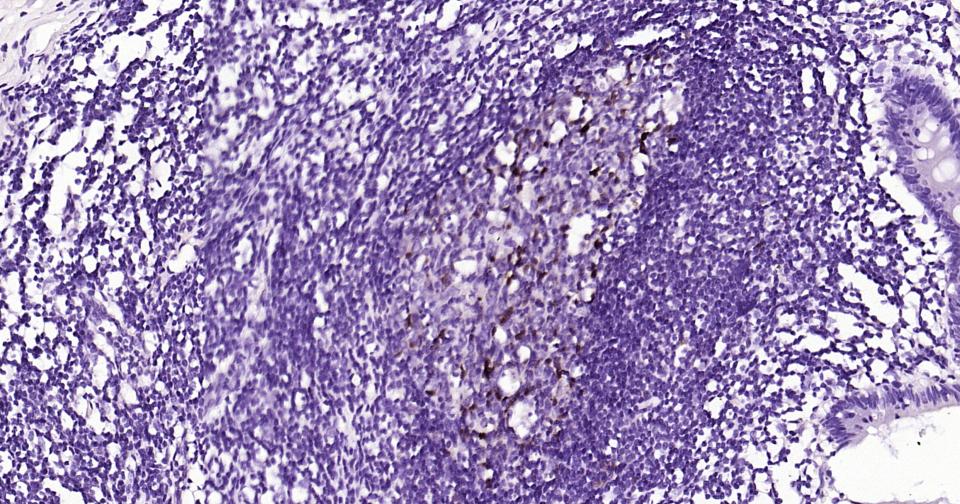

Paraformaldehyde-fixed, paraffin embedded Human Colon; Antigen retrieval by boiling in sodium citrate buffer (pH6.0) for 15 min; Antibody incubation with Parvalbumin Monoclonal Antibody, Unconjugated(bsm-61405R) at 1:200 overnight at 4°C, followed by conjugation to the bs-0295G-HRP and DAB (C-0010) staining.